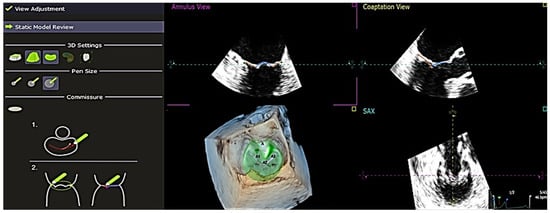

In addition to this, QLAB 13 also had the ability to perform quantitative analysis on a single frame throughout the cardiac cycle to obtain other parameters such as Ch-A, Ch-P, and inter-papillary distance. Mitral valve measurements were obtained after completing these stages (Figure 4). The results were exported in .txt format and arranged into measurement groups: “Annulus”, “Leaflets”, “Coaptation”, “Miscellaneous”, “Manual Measurements”, and “Dynamic Measurements”. These measurements were then extracted and compiled into an Excel sheet, summarizing the data for all 34 patients involved in the study. After collecting the 4D echocardiographic variables of all the patients, the data were compiled and edited meticulously and anonymously. The data were also checked again for any missing values or discrepancies. All omissions and inconsistencies were corrected and removed methodically. Additionally, other variables not derived directly from the software, such as indexed papillary muscle displacement, were manually calculated using the following formula: Indexed papillary muscle displacement = Inter-papillary distance/Body surface area. These values were then included in the data collection form.

Figure 4. Analysis of the final outcome of the generated measurements of the mitral valve—at the end of each analysis, complete measurements are automatically calculated. These are height of the leaflets and coaptation length, anteroposterior diameter, anterolateral–posteromedial diameter, sphericity index, non-planar angle, annulus circumference, annulus area (2D), annulus area (3D), and annulus height of the mitral valve estimated using the QLAB 13R software. The measurements can be exported in 2 types of files: DICOM SR and .txt format. AL-PM = anterolateral-posteromedial, AP = anteroposterior.